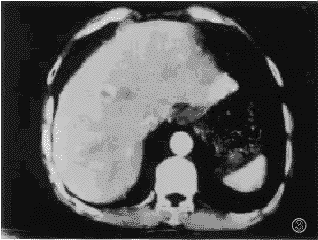

2.2.1 肝多发性血管瘤多期连续扫描表现:增强扫描中,血管瘤病灶共66个,其中21/66为小血管瘤,直径1.5~3.0cm,在增强扫描注射造影剂30秒、60秒时,15/21表现为均匀强化;有6/21表现为边缘不均匀强化,其中心可见低密度区。延迟至2分钟、5分钟扫描,病灶均表现为高密度或等密度灶。10~15分钟13/21表现为等密度,8/21表现为均匀低密度。44/66大血管瘤病灶,直径3.1~8.5cm,在30秒、60秒增强扫描,病灶边缘呈结节性强化,后期强化向中心扩展。37/44病灶在5~15分钟渐表现为等密度或稍低密度灶,8/44病灶延迟15分钟,中心仍见不规则低密度区。1/16例大血管瘤,直径4.2cm,在注射造影后,30秒、60秒表现为低密度,5~15分钟表现为边缘轻度强化(见图1~4)。

, 百拇医药

图1 多发性血管瘤.左外叶血管瘤病,30秒可见周边强化;

图2 左外叶血管瘤灶,60秒扫描病灶呈均匀高密度;

图3 右前叶血管瘤病灶,30秒可见病灶周边强化;

图4 60秒后病灶呈均匀高密度;